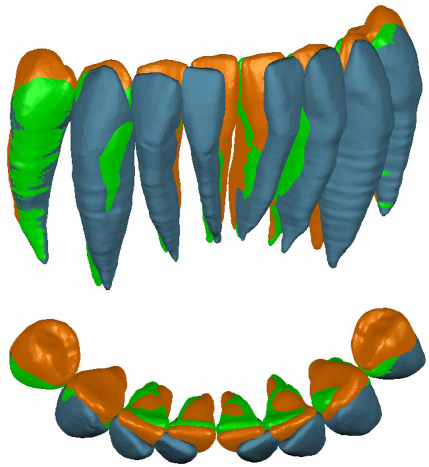

3. FOLLOW-UP AND OUTCOMES

Post treatment records (Fig. 6) demonstrated anterior leveling and alignment, accompanied by the complete closure of the diastema and the radiographic healing of the vertical bone loss (Figs. 7 and 8) between mandibular central incisors with a regeneration of the inter radicular bone of about 0.4 mm. Then, the patient was instructed to wear a clear retainer in the lower arch at night. Fig. (9) shows the superimposition of the initial, final and planned positions; it was evident that most of the planned movements were achieved, but not all.

All the coronal and radicular planned movements of the incisors occurred in a more or less comparable way to the virtual setup (Fig. 10). The most effective were the mesial and lingual body movement of the incisors (98 and 97%) and the least effective was the bodily intrusion movement of the incisors (54%), and there were no unexpected movements in these teeth. The rotation of the incisors around its vertical axis showed a high degree of predictability (75%) and torque movements occurred in the incisors (76%). The tip movement occurred in 67% of patients compared to the virtual setup.